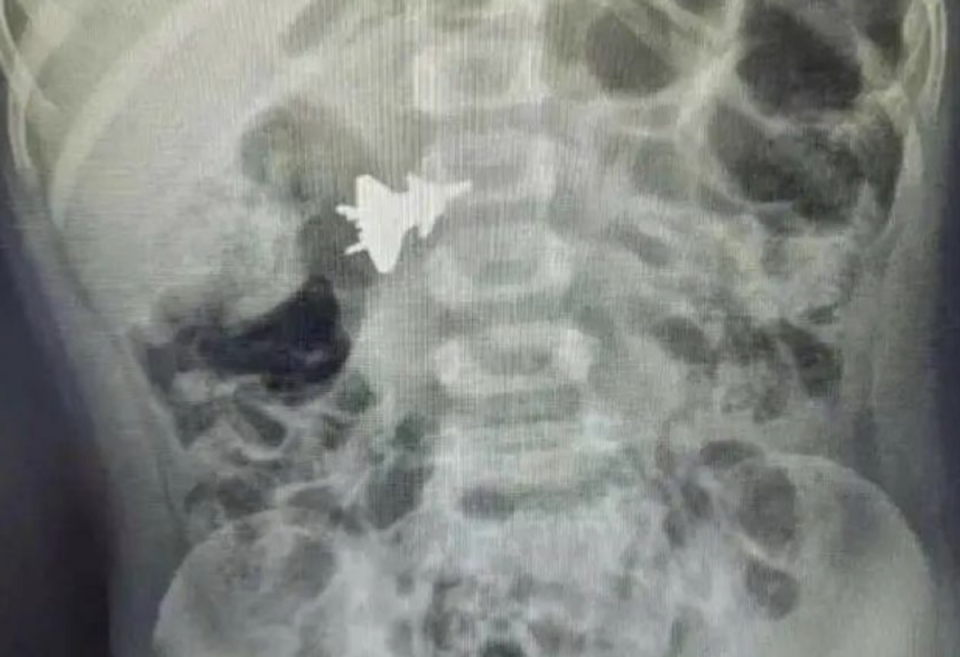

“F-35锁定歼-20”的真相:一场误解 让我们回到2023年6月的那条推文。这条推文声称,日本空自F-35战机通过红外成像系统锁定了中国歼-20战机,且歼-20的飞行员对此毫不知情。 然而,经过进一步核实,真相却大大出乎意料。 这张所谓的“F-35锁定歼-20”的图像,实际上是一张普通的CT扫描图。 2023年6月,一名中国广西的4岁小孩不小心吞下了一架歼-20模型玩具,家属带其去医院拍摄了CT扫描。 这个CT扫描图后来意外流传到网上,经过一些不明身份的人篡改和恶搞,渐渐就误传为F-35通过EOTS系统,拍摄到了歼-20图像。 这些无知的网友根本不懂红外成像的特点,也没有对这张图进行专业的分析,直接将其误解为F-35锁定歼-20的证据。 真实的EOTS成像与这张CT图截然不同。 EOTS的图像通常能够呈现目标的层次感,而CT扫描则只有模糊的轮廓,根本无法清晰展示战机的外形。任何有军事常识的人都能一眼识破这场骗局。 所以与其相信这篇推文的说法,不如相信小编是秦始皇! 歼-20的隐身能力在实际战斗中的应用 2022年3月,关于中美隐形战斗机在东海相遇的报道引起了国际社会的广泛关注。 当时,美国太平洋空军司令威尔斯巴赫在一次讲话中提到,F-35战机与歼-20在东海上空发生了近距离相遇,他对歼-20的表现给予了高度评价。 他称歼-20“飞行非常专业”,并且特别提到歼-20的指挥控制系统和空警-500预警机在协同作战中的作用,让他印象深刻。 歼-20能够在与F-35的空中对峙中占据上风,离不开空警-500预警机的支持。 空警-500能够为歼-20提供强大的远程目标探测能力,确保歼-20能在敌人尚未察觉的情况下发现并锁定目标。 这种协同作战模式让歼-20在战斗中具备了更强的远程作战能力,也让F-35等敌机在面对中国空军时,处于相对不利的局面。 未来空战:歼-20的优势与挑战 未来的空战将不仅仅是战机之间的较量,更是电子战、信息战的全面竞争。 隐身技术将继续进化,歼-20作为中国空军的核心力量,将在未来的空战中发挥至关重要的作用。 随着技术的不断进步,歼-20将进一步强化其隐身能力和作战半径。 F-35虽然在多任务能力上有优势,但其隐身性能和机动性相对较弱,尤其在面对像歼-20这样的空优战机时,其短板可能会暴露出来。 回到那场“F-35锁定歼-20”的传闻,这场误解背后,不仅有误传的图片,还有对技术细节的缺乏理解。 更重要的是,一些国人对歼20的不自信,才会导致谣传越传越大。 可实际上,歼20的性能并不差,甚至在隐身能力与协同作战方面,相较F-35是有领先的。 而在未来的空战中,歼-20凭借其先进的技术和战术运用,也将保持领先地位。 |